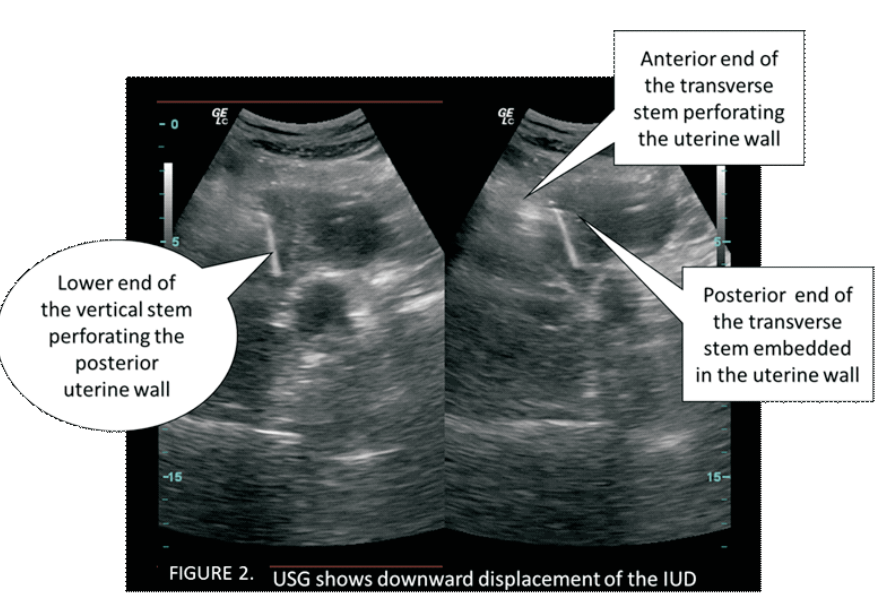

Secondary perforation with post placental intra uterine device: A case report

Sujnanendra Mishra (Author)

1635-1638